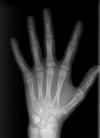

HWZ

Eine besondere Aufnahme ist das Röntgen der Handknochen zur Bestimmung des vorhandenen Wachstums des Patienten, da bestimmte kieferorthopädische Maßnahmen das Wachstum für den Erfolg erfordern (z.B. Korrektur der Unterkieferlage). Daneben ist es möglich, die spätere Körpergröße des Kindes zu berechnen.